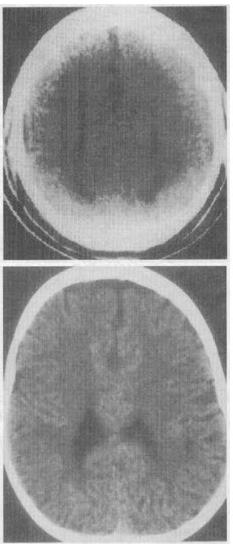

患儿男性,19个月。至今不能站立、不会说话。根据CT扫描所见〔见图),应诊断下列哪一种疾病()。

A:灰质异位

B:脑裂畸形

C:多小脑回畸形

D:结节性硬化

E:胼胝体发育不良